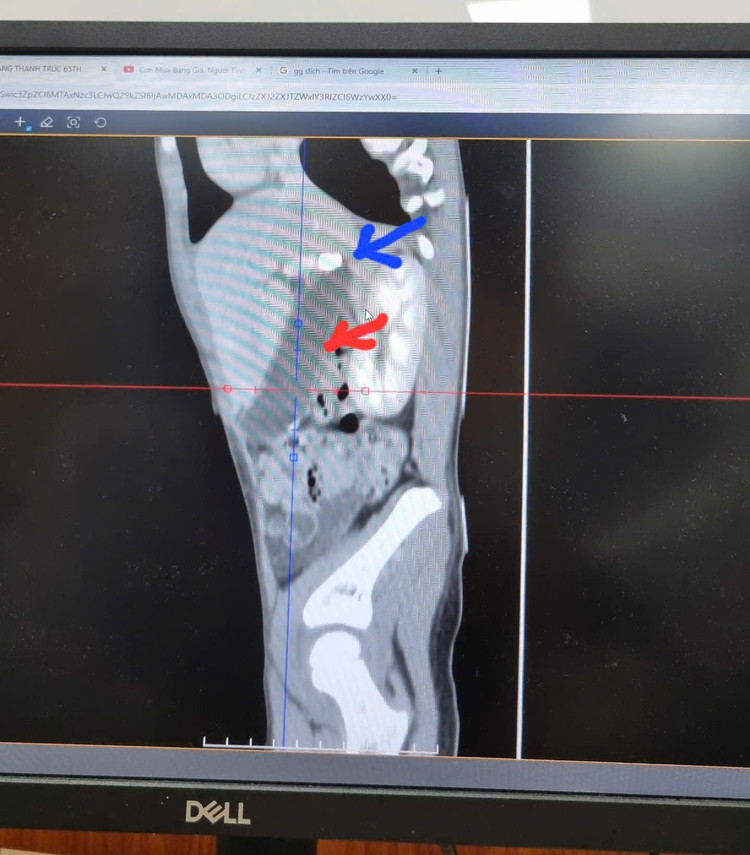

| Sỏi túi mật trên màn hình - Ảnh BVCC |